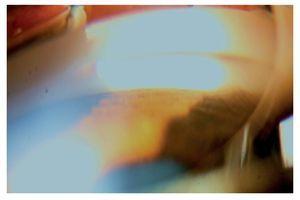

Hombre de 13 años de edad, sin antecedentes heredofamiliares ni personales patológicos de importancia. El motivo de consulta fue la disminución progresiva de la agudeza visual de meses de evolución, acompañado en ocasiones de dolor periocular intermitente. A la exploración física se encontró una talla de 1.52 m, la cual se encuentra dentro de la percentila 50 para la edad, así como una discreta braquidactilia en ambas manos. La exploración oftalmológica reveló: agudeza visual de 20/400 en ambos ojos y una agudeza visual mejor corregida de 20/30 y 20/40 respectivamente, con una refracción de -11.00 = -0.75X145° en OD y -11.00 = -2.50X5° en OI. La posición primaria de la mirada en ortoposición y los movimientos oculares fueron normales. La presión intraocular fue de 26 mmHg en OD y 21 mmHg en OI. El segmento anterior de ambos ojos bajo lámpara de hendidura, mostró una cámara anterior estrecha, tanto en la periferia como en el centro (Figuras 1a y 1b) con un ángulo iridocorneal en ambos ojos de 0 en los 360° (Figuras 2a y 2b). En segmento posterior de ambos ojos encontramos una excavación papilar de aproximadamente 6/10, con un defecto en la capa de fibras nerviosas evidenciada por las fotografías libres de rojo (Figuras 3a y 3b). El paciente fue tratado inicialmente mediante la realización de iridotomías con láser de YAG en ambos ojos y tratamiento tópico con una combinación brimonidina-timolol-dorzolamida, acudiendo nuevamente a consulta dos días posteriores al tratamiento encontrando una presión de 13 mmHg en ambos ojos con las iridotomías permeables (Figura 4).

¿ Figura 4. Fotografías clínicas antes y después de las iridotomías.